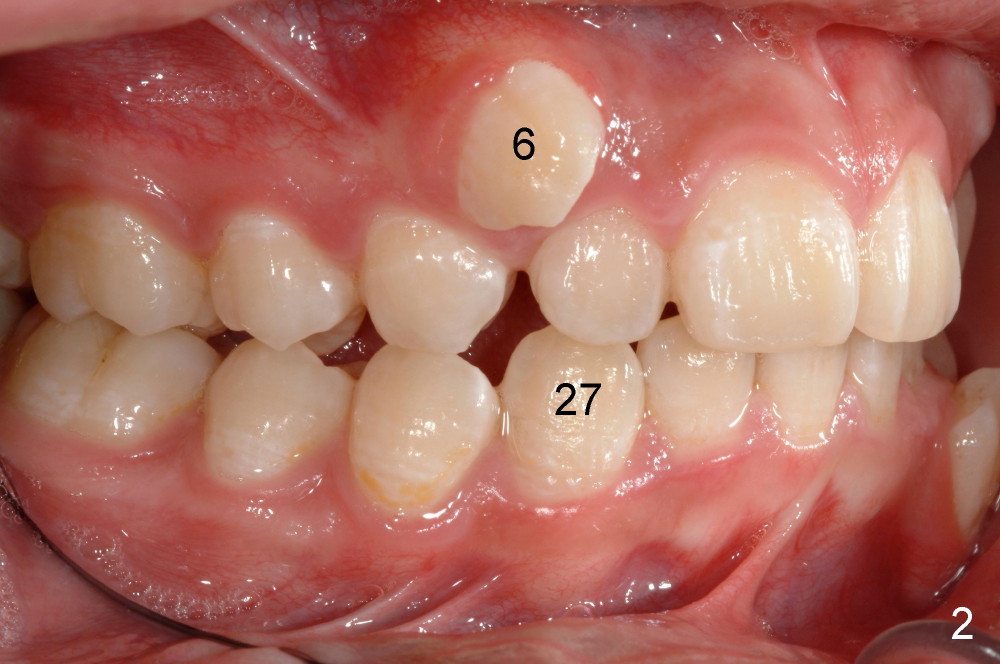

Tim: Thank you so much for the tip.  It appears that an alastik is placed between #6 bracket and the upper AW.  Can you recommend surgical exposure of #11?

We are teasing tooth #6 down initially with a light elastic force. This will minimize any reciprocal forces on the anterior teeth. I do not want to intrude the incisors while extruding 6. That would potentially open the bite.

You will see tooth #11 continue to erupt spontaneously. In the initial photos, it was not visible. It was simply mechanically blocked out. And the tissue will b the best when the tooth erupts spontaneously. Bet on 11 to erupt😉 and a couple more mm of eruption and I will b able to place a button and like 6, begin to tease down faster.